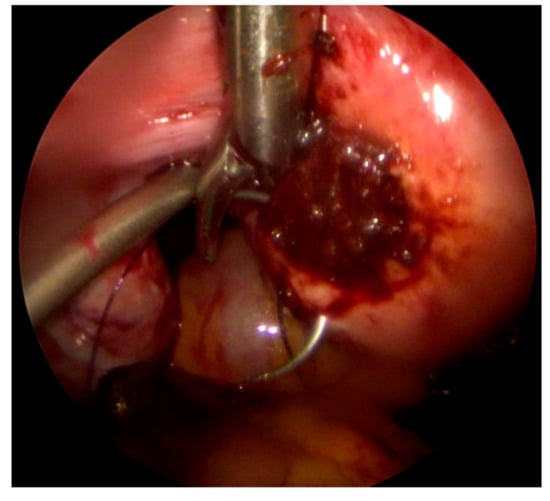

Disturbed Interstitial Pregnancy: A First Case of Successful Treatment Using a Mini-Laparoscopic Approach

2. Case Report